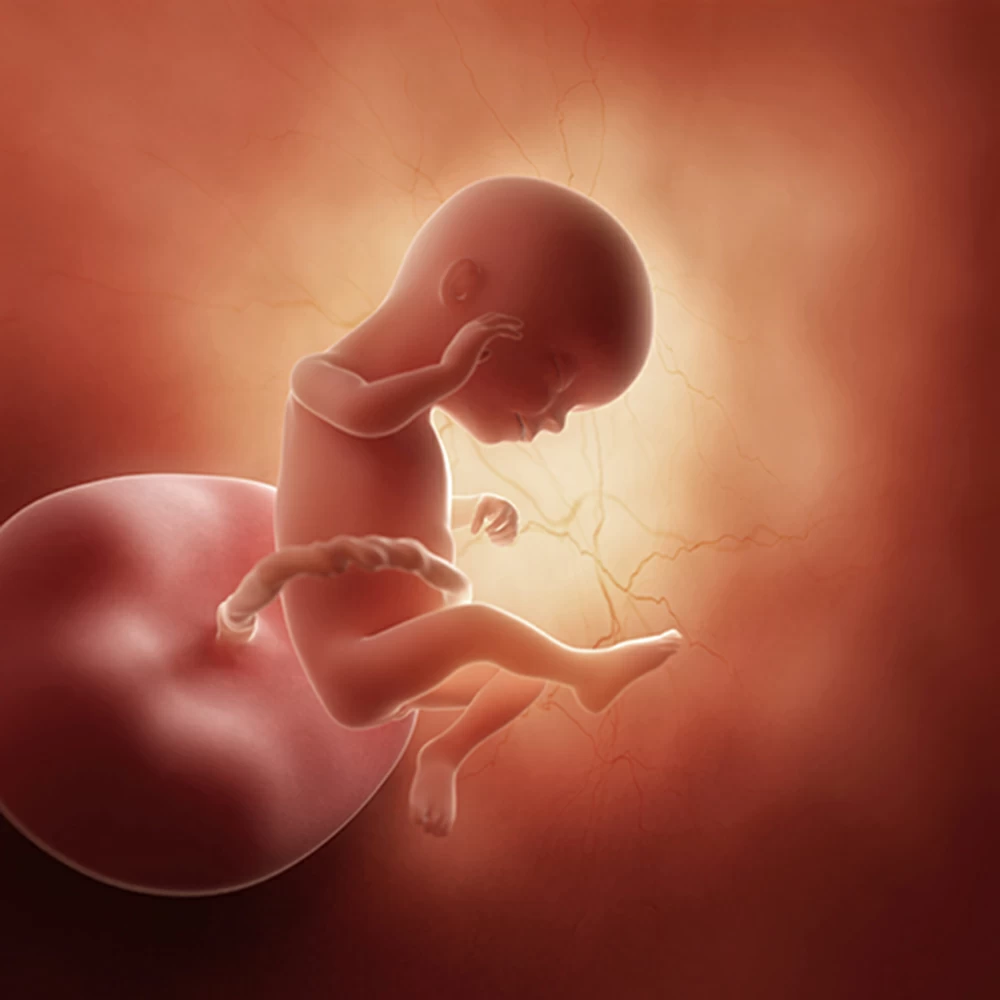

Тело плода остается непропорциональным: мелкое туловище, большие размеры головы, длинные руки и короткие ноги, согнутые во всех суставах и прижатые к животу.

Эмбрион согнут еще дугообразно, на тазовой части тела имеется маленький хвостик. Размер головы составляет не менее всей половины зародыша. Длина от темени до крестца к концу недели вырастает до 13-15 мм.